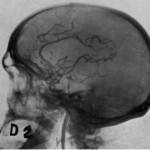

figure 2